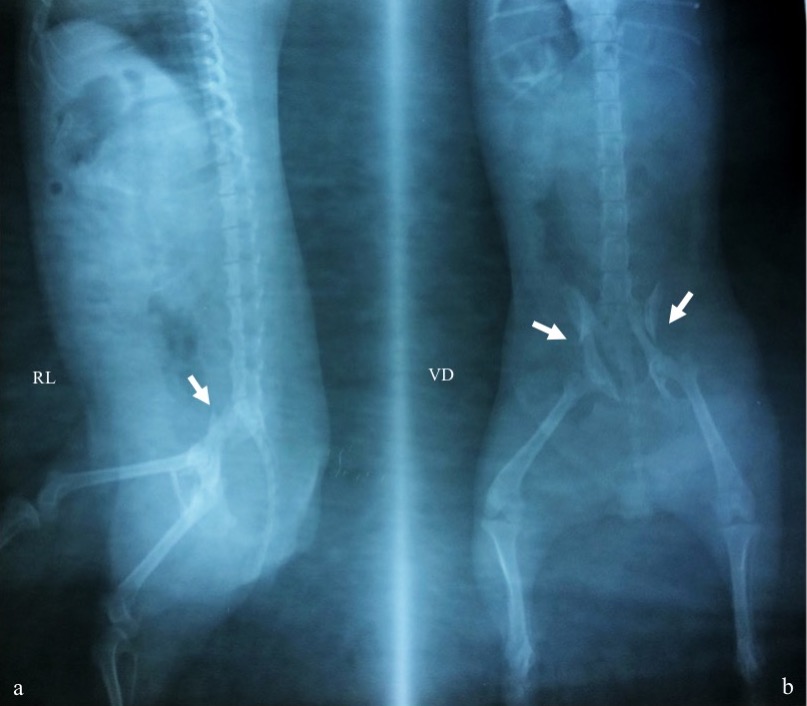

Fraktur adalah terputusnya kontinuitas jaringan tulang yang umumnya disebabkan oleh trauma. Anjing ras Yorkshire berumur 2,8 tahun dengan bobot badan 2,6 kg menunjukkan gejala klinis tidak bisa berdiri, kedua ekstremitas posterior mengalami diplegic lameness dan anjing hanya bertumpu dengan ekstremitas anterior. Anamnesis dengan pemilik hewan mengatakan anjingnya mengalami trauma akibat tertimpa tangga. Hasil pemeriksaan radiografi dengan posisi hewan right lateral dan ventro dorsal menunjukkan fraktur bilateral pelvis berbentuk oblique pada tulang ilium. Penanganan yang dilakukan adalah dengan metode open reduction internal fixation menggunakan bone plate 2.0 veterinary cuttable plate (VCP) dengan screw 2.0 mm cortical non-self-tapping pada kedua sisi tulang ilium. Hari ke-3 setelah tindakan bedah, pasien mulai dibantu untuk berjalan sebagai upaya melatih pergerakan ekstremitas posterior. Satu minggu setelah bedah, pasien sudah bisa berjalan dan menunjukkan perkembangan yang baik. Penanganan bilateral fraktur pelvis berbentuk oblique pada bagian ilium dapat ditangani dengan bone plate dan screw.